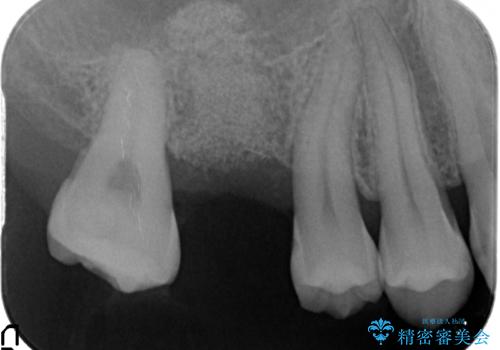

- 右上の歯を喪失し機能回復を希望され来院されました。

骨量が不十分であった為、ソケットリフトを併用しインプラントによる補綴計画を立てます。

ソケットリフトについて

上顎のインプラントは、上顎洞底までの距離が短い場合ソケットリフト法を行い骨量を増やしたのちにインプラント埋入を行うことでより長期的な予後を見込むことができます。